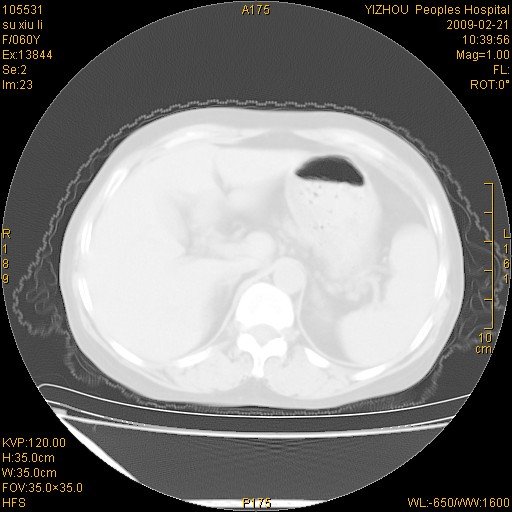

标题: CT18259:两肺间质纤维化? [打印本页]

标题: CT18259:两肺间质纤维化?

女,60岁,反复咳嗽1月。

两肺支扩,以肺为著合并双肺较广范纤维化病变。建议除外结核等病变。

间质性肺炎

符合间质感染,部分纤维化表现

特发性间质纤维化

特发性间质纤维化伴支扩!

间质性肺炎或特发性间质性肺炎